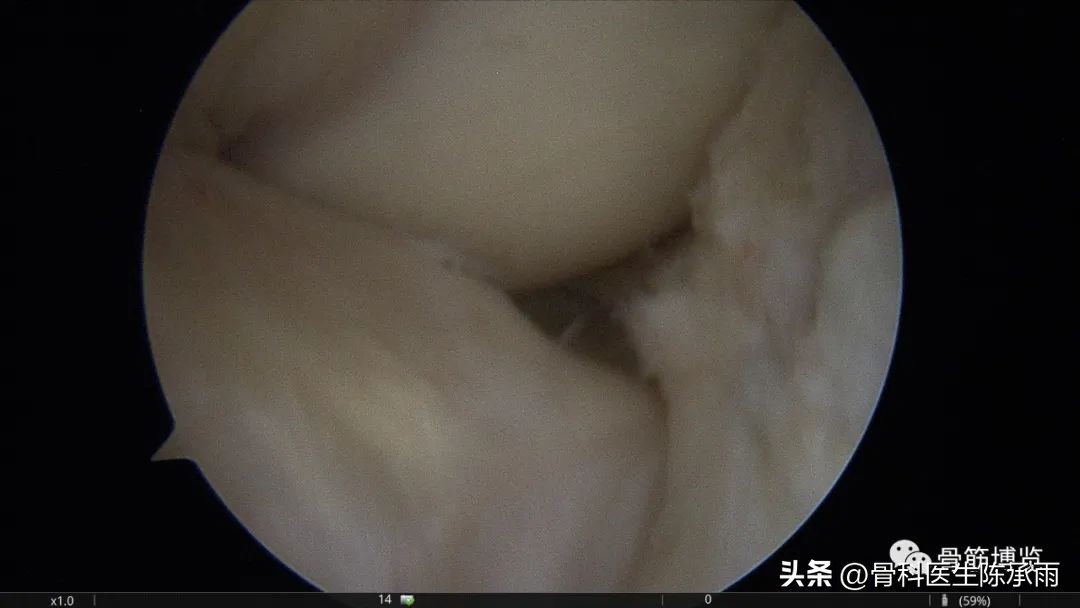

本例为内侧半月板前角巨大囊肿,关节镜下行半月板囊肿引流减压+囊肿前壁及囊壁滑膜切除+半月板缝合术。术中切除全部囊壁内滑膜及前壁及大部分后壁,保留部分后壁组织,以保证半月板前角缝合可靠及稳定。

术中情况

半月板囊肿分型决定了治疗方法的选择,对于前两种半月板囊肿因伴有半月板的损伤治疗方法相对复杂,半月板囊肿合并的半月板损伤多为水平撕裂或复杂撕裂,而且病史较长,因此需严格掌握缝合手术的指证。手术操作要点:采用常规的髌下内侧和髌下外侧入路,探查关节内囊肿和半月板撕裂的大致范围;使用刨刀细致地将囊肿切除,尽量彻底切除囊壁,充分敞开囊腔,避免囊肿复发,囊肿内可有分房或分隔现象,注意避免遗漏。注意在手术时尽量保留冠状韧带,避免冠状韧带的广泛缺损;进一步仔细探查损伤的半月板组织,明确撕裂的范围在红﹣红区或红﹣白区,对于超出上述范围的损伤或半月板的复杂撕裂及水平撕裂,放弃缝合手术,如条件许可时可在切除部分半月板(如切除水平撕裂的两片中不稳定的一片)的基础上进行缝合手术。然后以刨刀或磨钻小心修整损伤的半月板组织,使对合面整齐并显露新鲜组织;髌下外侧人路置人工作套管,附加经髌韧带的正中入路,严格解剖复位。经正中人路置人探针,固定半月板撕裂部位,使用肩袖缝合器经髌下外侧入路工作套管,缝合器尖端首先由半月板前缘和冠状韧带的交界处穿人半月板下表面后,越过半月板裂隙,在对侧由下到上穿出半月板上表面,经工作套管将线导出,体外打 Duncan 结,推线器将线结推人至半月板前缘处拉紧,再打两个套结,剪断缝线。两缝线之间间距8 mm 。滑膜囊肿的手术操作相对简单:镜下切除囊肿后,将半月板与冠状韧带之间的缺损区缝合。